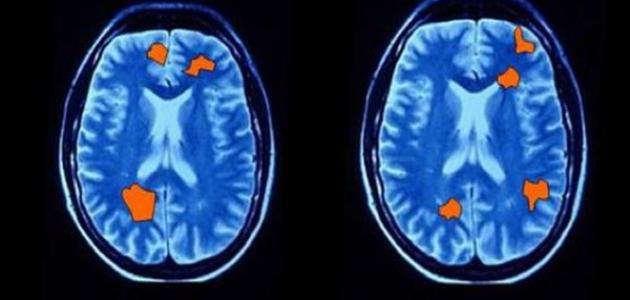

عند الحديثِ من الناحية العلميّة التي أثبتتها الدراسات والأبحاث، فليس هناك إلا طريقةٌ واحدة تُستخدمُ من أجل تحديد نوع الجنين، ألا وهي استخدام السونار، فالسونار يقوم من خلال الموجات الفوق صوتيّة بنقل انعكاسات الجنين وشكله وتحرّكاته من داخل الرحم إلى شاشة خاصّة، ومن خلال النظر إلى الشاشة يستطيع الطبيب تحديد نوع الجنين، وتعدّ هذه الطريقة أدقَّ من الطرق الاجتماعيّة التقليديّة المتوارثة.